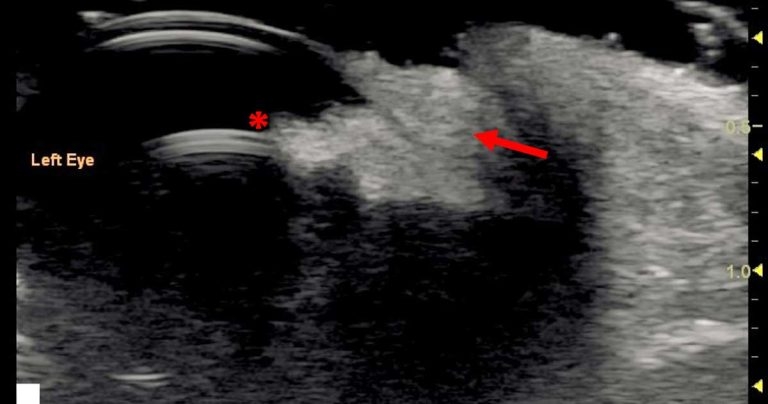

Intraocular neoplasia can be focal or diffuse and affect different parts of the eye (Figure 15).

Additionally to visible masses and structural changes to the ocular anatomy, neoplasia can cause glaucoma, haemorrhage and uveitis.

Ultrasound is extremely valuable in evaluating neoplastic pathology as it can help to define the extent of the pathology, especially when normal structures are obscured.

Choroidal melanocytic neoplasia is the most common ocular neoplasia seen in dogs and cats8,9. Ciliary body adenomas/adenocarcinomas are the second most common in dogs10.

The ultrasonographic appearance of neoplasms can vary in echogenicity and masses can cause deformation of the posterior globe.